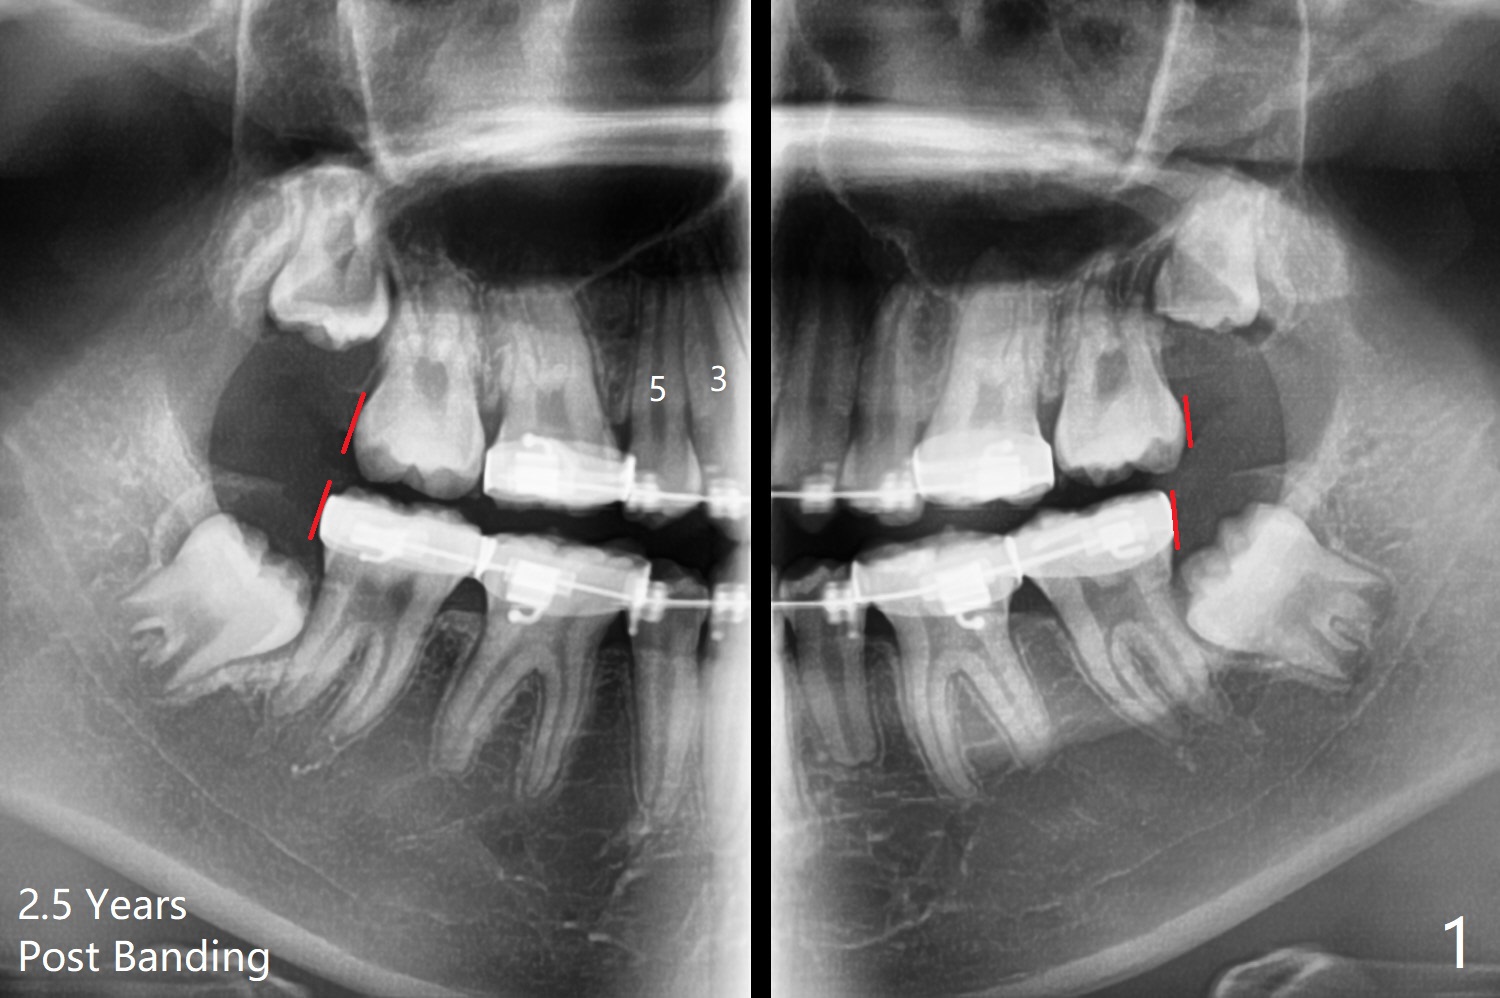

While the left posterior interdigitation is normal, the right is a half tooth off (Class II) 2.5 years post banding (16 years old, male, Fig.1). The upper midline remains left. The roots of the upper anterior teeth are within normal limit. UR8 will be extracted with bone graft (sticky bone; Fig.2). A 8 mm mini implant or a DIO 1-piece implant with ball abutment will be placed in the same appointment if possible (red circle). With a closed coil spring, UR3-7 or 1-7 will be distalized en bloc (Fig.3). Take photos for the occlusion: right, middle and left.